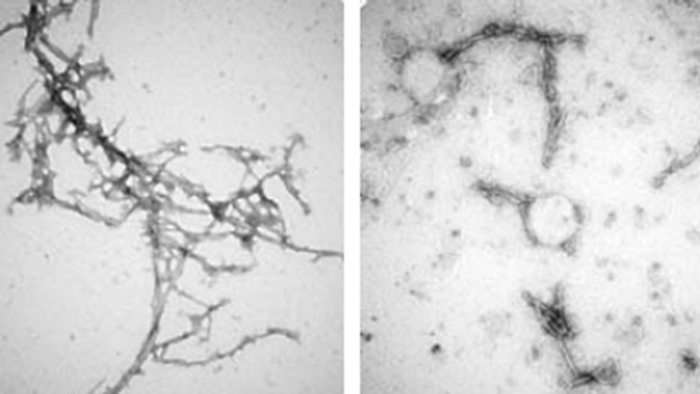

- Caption: Disulfide Bond-free and Fibril-specific Nanobodies Prevent the Prion-like α-synuclein Spreading

Proteins called antibodies help the immune system find and attack foreign pathogens. Mini versions of antibodies, called nanobodies — natural compounds in the blood of animals such as llamas and sharks — are being studied to treat autoimmune diseases and cancer. Now, Johns Hopkins Medicine researchers have helped develop a nanobody capable of getting through the tough exterior of brain cells and untangling misshapen proteins that lead to Parkinson’s disease, Lewy body dementia, and other neurocognitive disorders caused by the damaging protein.

“The success of PFFNB2 in binding harmful alpha-synuclein clumps in increasingly complex environments indicates that the nanobody could be key to helping scientists study these diseases and eventually develop new treatments” says Mao, associate professor of neurology.